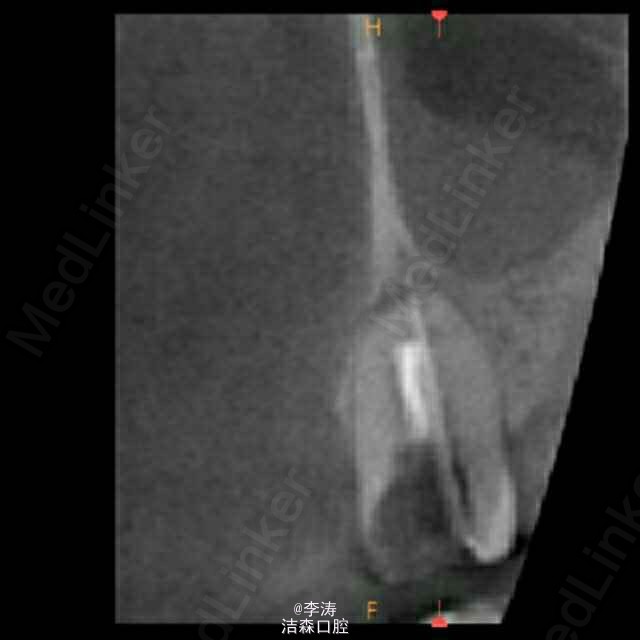

过台阶根管再治疗一例

15牙因根管治疗后牙折裂,行根管再治疗

年轻恒牙;根管再治疗;消除台阶